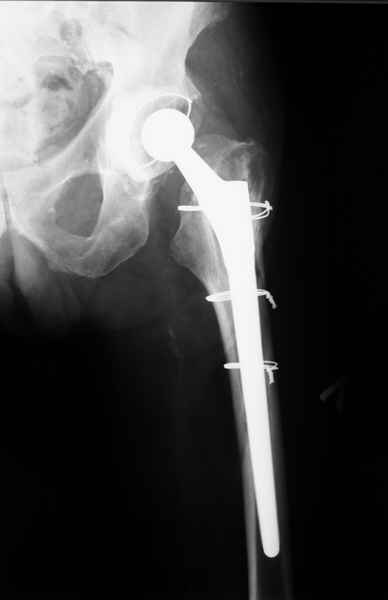

Можно уверенно рассчитывать на сращение фрагментов бедра между собой. Можно ли рассчитывать на реинтеграцию имеющейся ножки в проксимальном отделе - действительно вопрос открытый. Но во всяком случае ножка будет заметное время стабильной за счет дистальной фиксации. Будет ли это время достаточно на всю оставшуюся жизнь пациента - трудно предугадать.

Но, как Александр Виноградский справедливо заметил, после сращения бедра появляется возможность поставить даже обычную ножку большего размера.

Уважаемые коллеги, продолжая дискуссию, начатую на "Вреденовских чтениях", хочу сказать, что принципиально сущестует два возможных варианта лечения.

1.Остеосинтез на ножке. Мне кажется, что применительно к этому случаю малоперспективный вариант. Синтез хорош, когда можно его выполнить в малоинвазивном исполнении и достигнуть стабильности. Действительно, если ножка б/цементной фиксации после этого не будет иметь фиксации, то ревизия не будет иметь проблем. В представленном случае стабильность синтеза сомнительная, а проведение доп.иммобилизации приведет к контрактуре суставов.

2. Применение ножки дистальной фиксации, мы отдаем предпочтение ножке Вагнера с фиксацией проксимального отдела на ножке. Более травматичное вмешательство, но при стабильной фиксации ножки реабилитация идет в обычном режиме.

Хочется показать два подобных случая, П-ка З. 72 лет и п-т Г. 80 лет. Сразу принимаю замечание, что это были ножки цементной фиксации, просто под руками не было бесцементника.